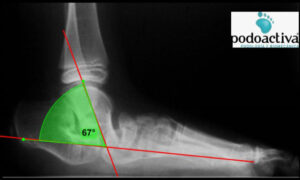

A nivel radiológico se pueden obtener medidas alteradas de diversos ángulos en proyecciones dorsoplantar y sagital. Prestaremos especial atención al ángulo radiográfico sagital TAMBA:

– El ángulo del eje del astrágalo con la base del primer metatarsiano (TAMBA):

– Entre 30º y 60º lo consideraremos astrágalo oblicuo.

– Valores por encima de 60º los consideraremos astrágalo vertical.